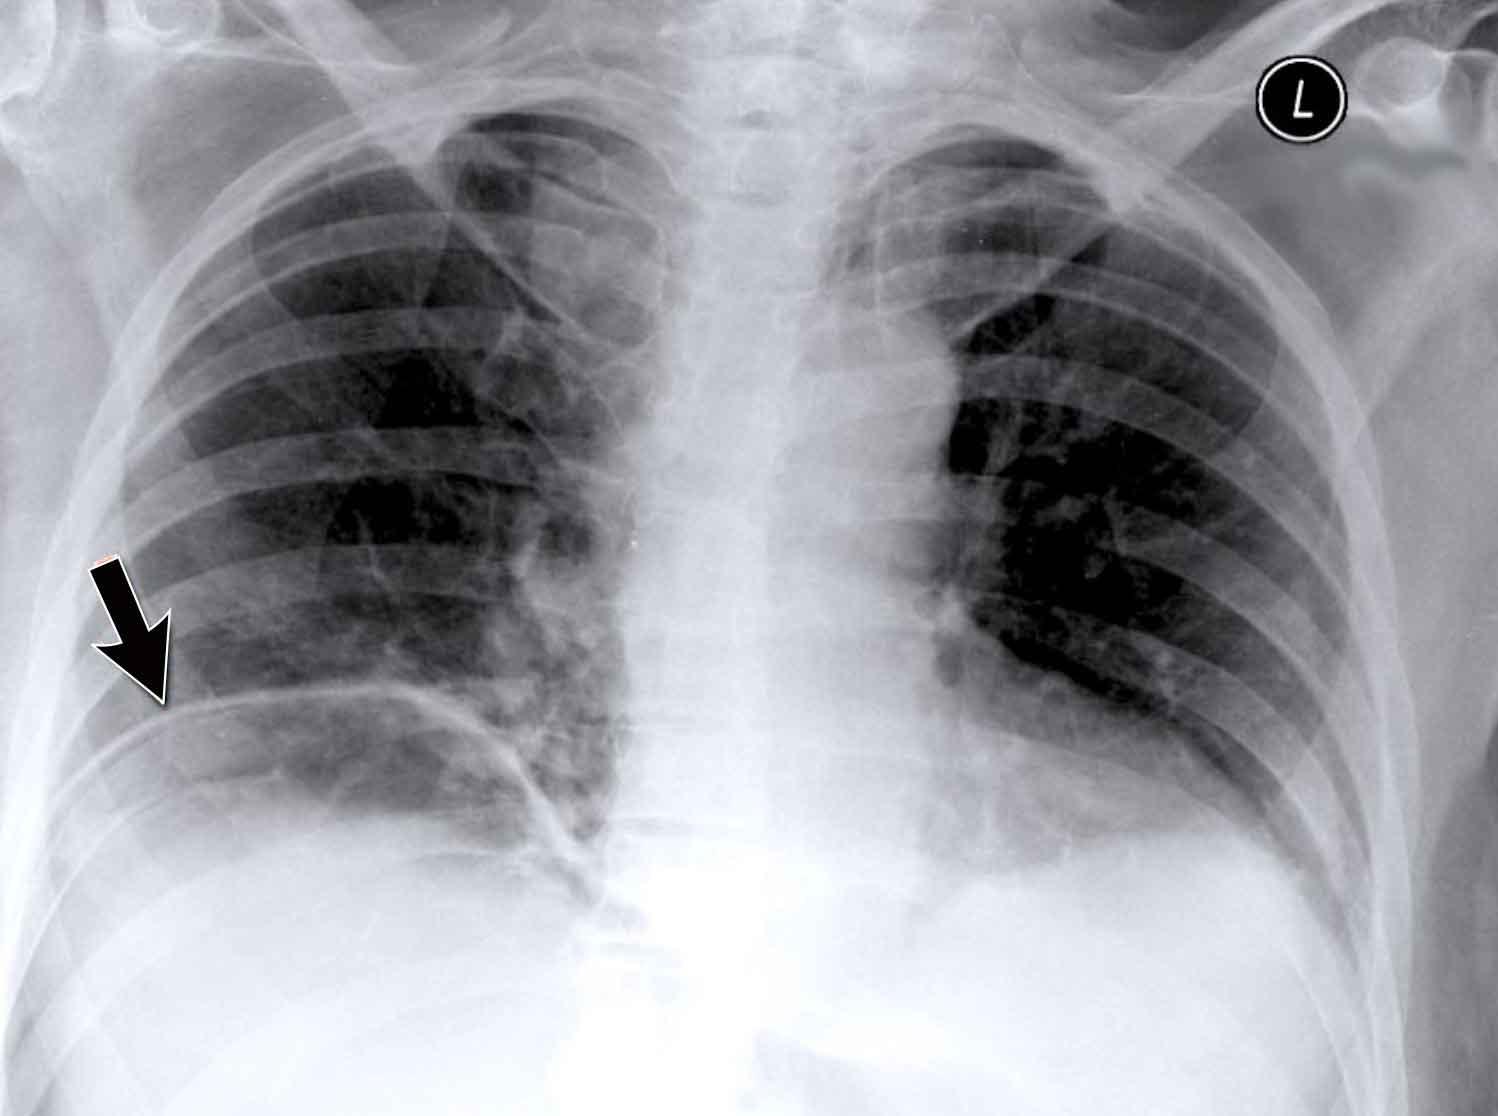

Vùng Khuất (2): Tổn thương Thùy Dưới Phải

Ví dụ này minh họa một khối lớn ở thùy dưới phải khó nhận biết trên phim PA nếu không chú ý kỹ đến các vùng khuất.

- Khi quan sát ban đầu, tổn thương không rõ ràng.

- Tuy nhiên, khi tập trung xem xét vùng dưới hoành và vùng sau tim, bất thường trở nên rõ ràng hơn.

- Phóng to hình ảnh để quan sát tốt hơn.

Ca lâm sàng

Bệnh nhân nam 70 tuổi nhập viện sau khi ngã xuống cầu thang, than phiền đau dữ dội vùng hông phải.

Kết quả hình ảnh

- Trên phim X-quang ngực tư thế thẳng (PA), không thấy hình ảnh ngón thứ năm bên phải.

- Trên tư thế nghiêng, có hình ảnh tăng tỷ trọng chiếu lên vùng cột sống ngực dưới.

Chẩn đoán của bạn là gì?

Các dấu hiệu phù hợp với xẹp phổi thùy dưới phải.

Trên tư thế thẳng (PA), lưu ý bờ tim phải có hình dạng bất thường. Động mạch phổi liên thùy phải không được nhìn thấy — do nó không được bao quanh bởi nhu mô phổi thông khí, mà thay vào đó là thùy dưới phải bị xẹp, nằm kề cạnh nhĩ phải.

Trên phim chụp kiểm tra, thùy dưới phải đã nở lại và hình ảnh xẹp phổi đã hồi phục.

Điều này gợi ý rằng xẹp phổi nhiều khả năng là do giảm thông khí sau chấn thương kèm theo nút nhầy.

Cũng ghi nhận trên phim kiểm tra là sự tái xuất hiện của ngón thứ năm bên phải (mũi tên đen) và sự phục hồi bờ tim phải bình thường (mũi tên trắng), xác nhận thùy dưới đã nở lại.